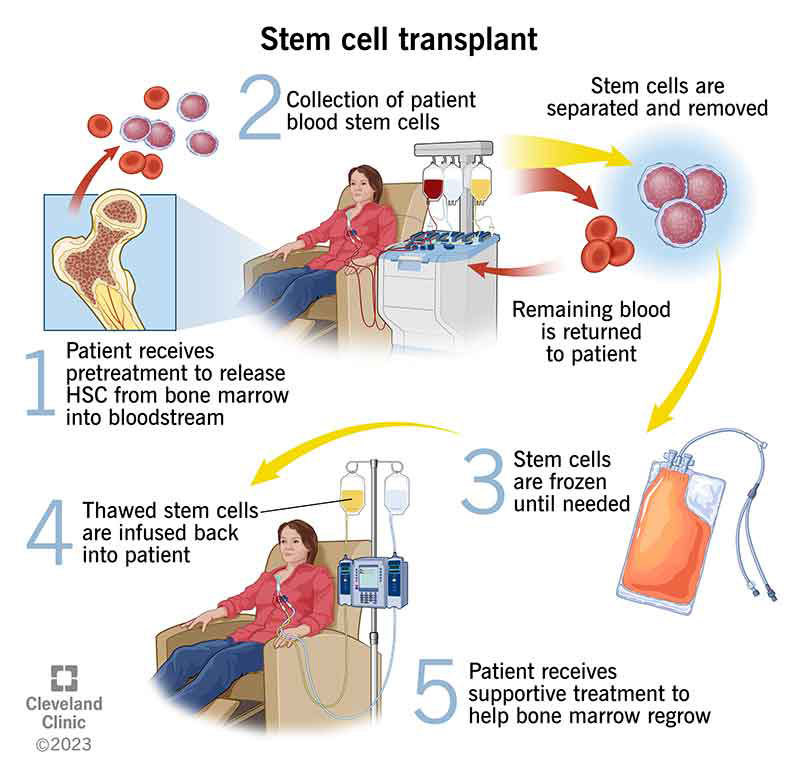

Stem Cell Transplant (Bone Marrow Transplant)